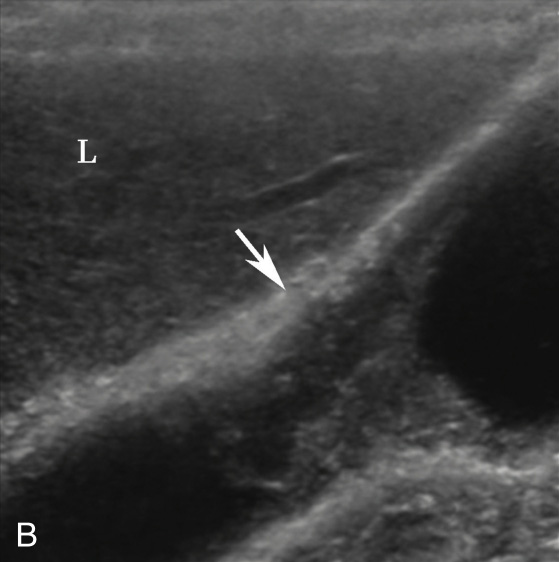

(1)局限型胆囊腺肌症:

好发于胆囊底部,灰阶超声图像通常呈边界清楚的低回声(图2-4-1A)。病变内部回声不均匀,能够观察到小片状无回声区,部分病变内可见点状高回声后伴彗星尾征(图2-4-1B)。CDFI通常无明显血流信号,部分病变内的点状高回声后方可见“快闪伪像”(图2-4-1C)。

图2-4-1 局限型胆囊腺肌症常规超声图像

A.胆囊底部低回声结节(箭头所示),边界清楚,形态规则;B.结节内可见点状高回声后伴彗星尾征(箭头所示);C.CDFI示结节内可见“快闪伪像”